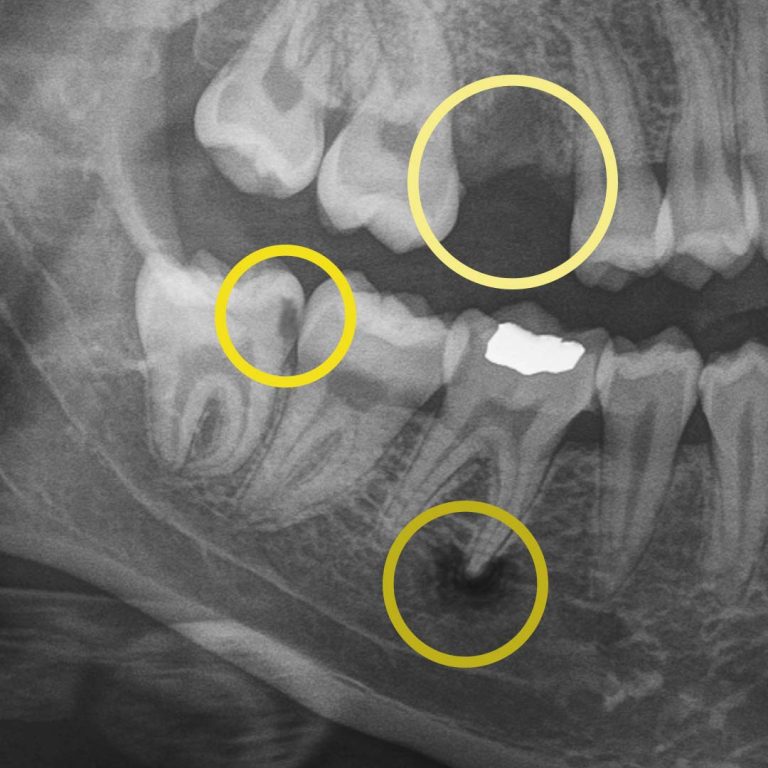

Digital X-rays allow us to look beyond what’s visible. They help us detect:

• cavities between teeth.

• early decay hiding under fillings or crowns.

• bone changes related to gum disease.

• infections at the root of a tooth.

• subtle cracks.

• wear patterns.

• missing primary teeth in children.

For example, during a routine digital X-ray, we may notice a small shadow between two teeth. To the naked eye, everything can look healthy, but that faint shadow often tells us the enamel in that area is starting to weaken. This is considered early-stage tooth decay, sometimes called early “caries.”

At your next X-ray visit, we’ll compare images to see whether that spot has stabilized or improved. If the area worsens and the enamel breaks down further, a small dental filling may be necessary to prevent deeper decay damaging the tooth structure. If the decay continues unchecked and reaches the inner portion of the tooth where the nerve lives, treatment becomes more complex, often requiring root canal therapy, which can be time-consuming, uncomfortable, and costly.

While catching early tooth decay is one of the most common reasons we rely on digital X-rays, it’s far from the only one. Dental imaging also helps us monitor bone levels to detect gum disease before it leads to tooth loss, identify disease that can’t be seen during an exam, and track hard and soft tissue changes caused by grinding, acid wear, or dietary habits. A complete set of digital X-rays is necessary every few years to ensure the health of all your teeth. This allows you to keep your natural teeth longer.